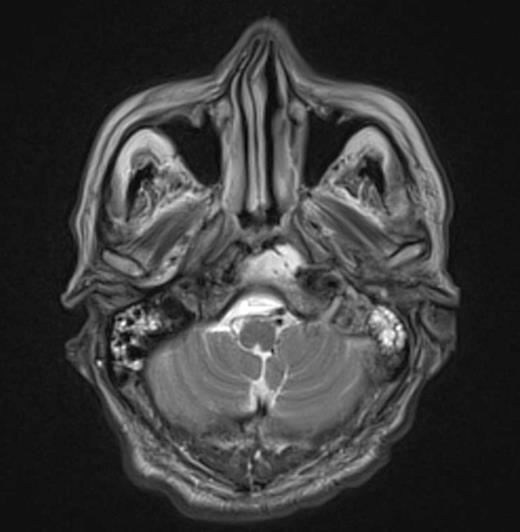

At the tertiary hospital the patient was found to be clinically wasted and weak. He also had rightward uvular deviation, absent gag reflex, weakness of the left sternocleidomastoid and trapezius, House Brackman grade 2 left facial nerve weakness and an immobile left vocal cord. This was the first time a cranial nerve examination was recorded. MRI and SPECT/CT with Gallium tracer was performed, the images acquired from which illustrate the severe extent of disease (figures 1 to 5).

He was diagnosed with MOE with extensive skull base osteomyelitis producing multiple lower cranial neuropathies. Biopsy performed by ORL/ENT surgeons grew Scedosporium apiospermum and given the extent of the infection a palliative approach was agreed upon with the patient and family.